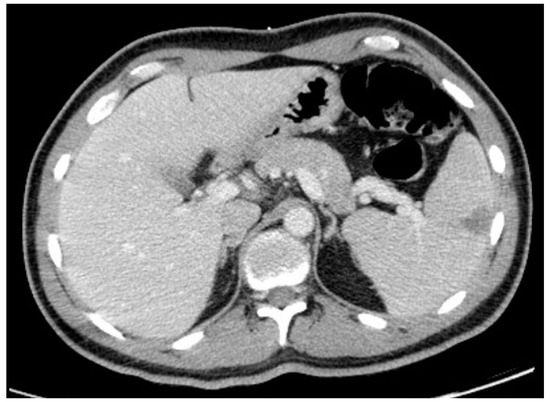

Thoraco-abdominopelvic CT showed mediastinal lymphadenopathies, the largest being 6 mm, and no abnormalities in the lungs. It also revealed a triangular hypodensity in the spleen with 4.1 × 4 cm, suggesting splenic infarction (Figure 2).

The appearance of a consumptive syndrome, always of great concern especially in a young patient, motivated further investigation. The finding of a splenic infarct in the thoraco-abdominopelvic CT, without any other significant findings, was the final clue connecting all the signs and symptoms and leading to the final diagnosis.

Figure 2. Thoraco-abdominopelvic CT showing splenic infarction.